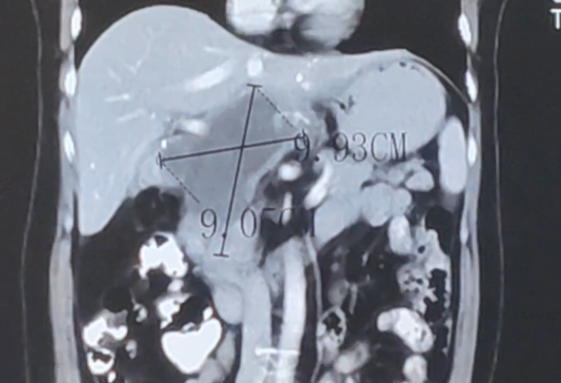

第1程治疗后,汪姐进食后恶心、呕吐的症状得到缓解。第2程治疗后,影像结果提示肿瘤缩小,多处可见明显坏死,胃腔也逐渐恢复正常。“比起开刀手术,那介入手术可轻松得多。”随着一次又一次的介入治疗,汪姐的情况一次比一次好。

▲2024年8月第2次疗程后